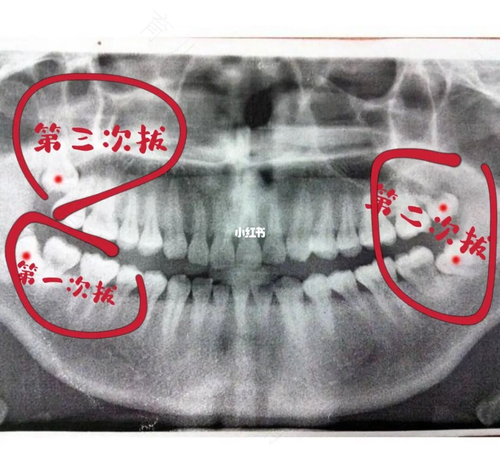

但是也有些特别情况是需要住院拔出智齿。比如:一次性拔出所有智齿,或者是智齿的位置比较低,紧挨着神经的位置,这时也需要住院拔出智齿。